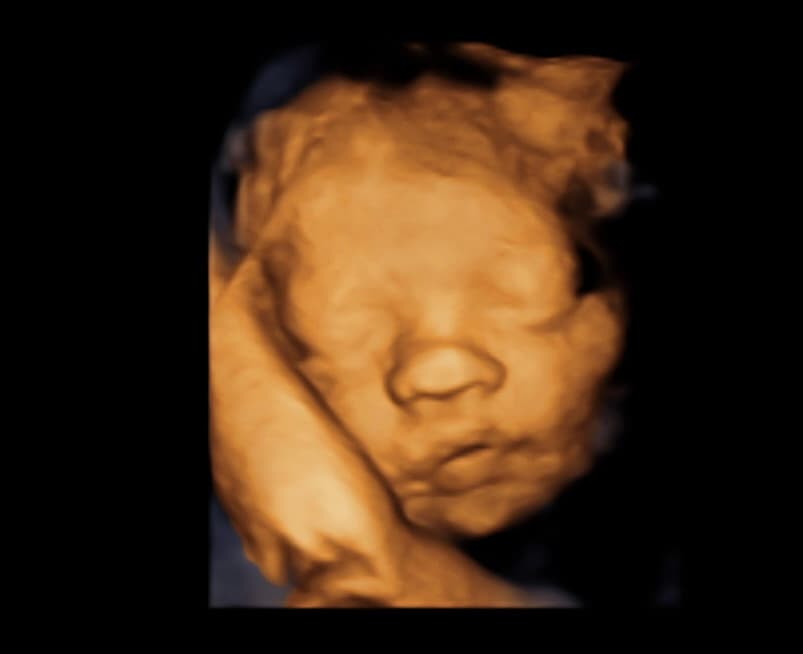

At Magnolia Fetal Imaging, we provide a warm, relaxing environment where you can bond with your baby through advanced 3D/4D & HD ultrasound technology. Our studio focuses on capturing precious keepsake moments for families — gender reveals, early looks, and high‑definition images you will cherish for a lifetime.

All sessions are non‑diagnostic and designed purely for bonding and keepsake entertainment.